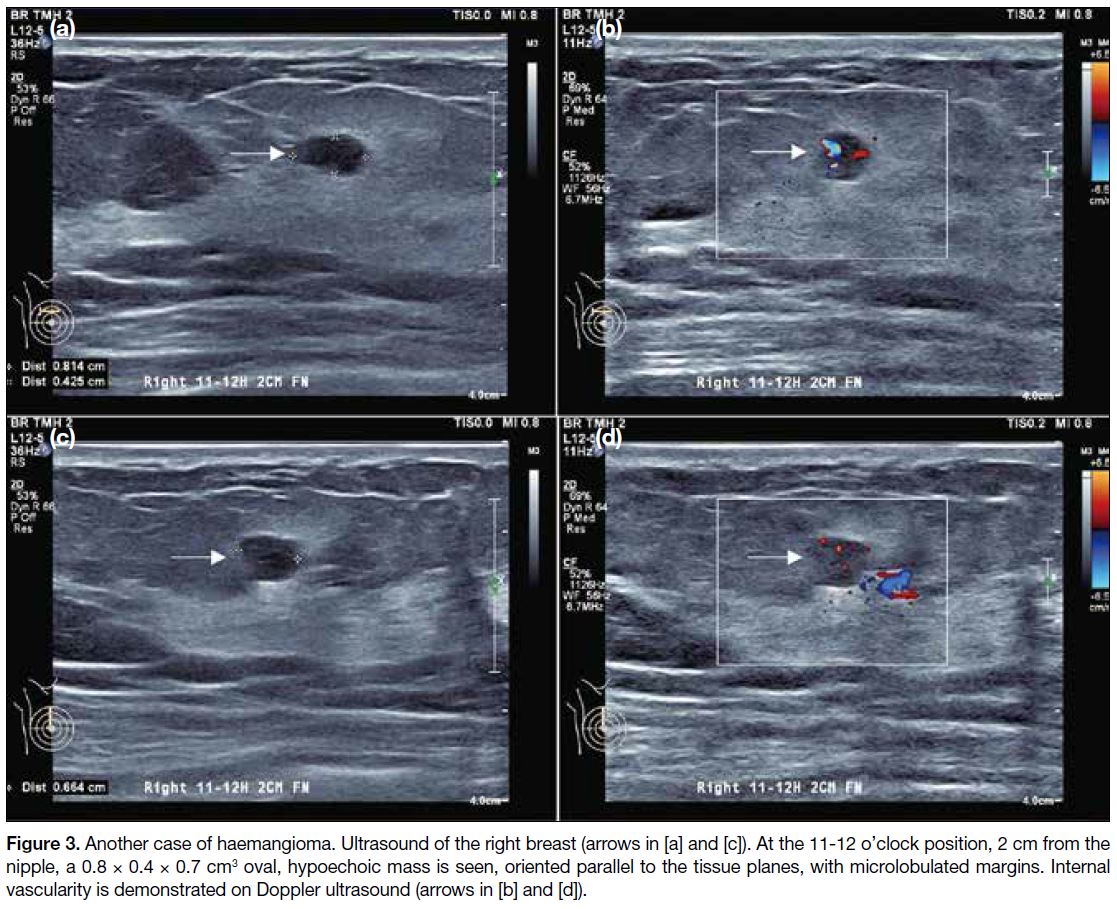

Sonographically, they are similar to their shape on

mammography and are oriented in a parallel manner

(Figures 2 and 3).[2] Their echogenicity is variable,[2] and

they may exhibit non-specific vascular flow.[3] Overall,

there are no definitive imaging features to suggest

benignity or malignancy. Histologically, these lesions

may present as a proliferation of variably sized, ectatic

blood vessels separated by fibrotic stroma.

Figure 3. Another case of haemangioma. Ultrasound of the right breast arrows in [a] and [c]. At the 11-12 o’clock position, 2 cm from the nipple, a 0.8

× 0.4 × 0.7 cm3 oval, hypoechoic mass is seen, oriented parallel to the tissue planes, with microlobulated margins. Internal vascularity is

demonstrated on Doppler ultrasound (arrows in [b] and [d]).